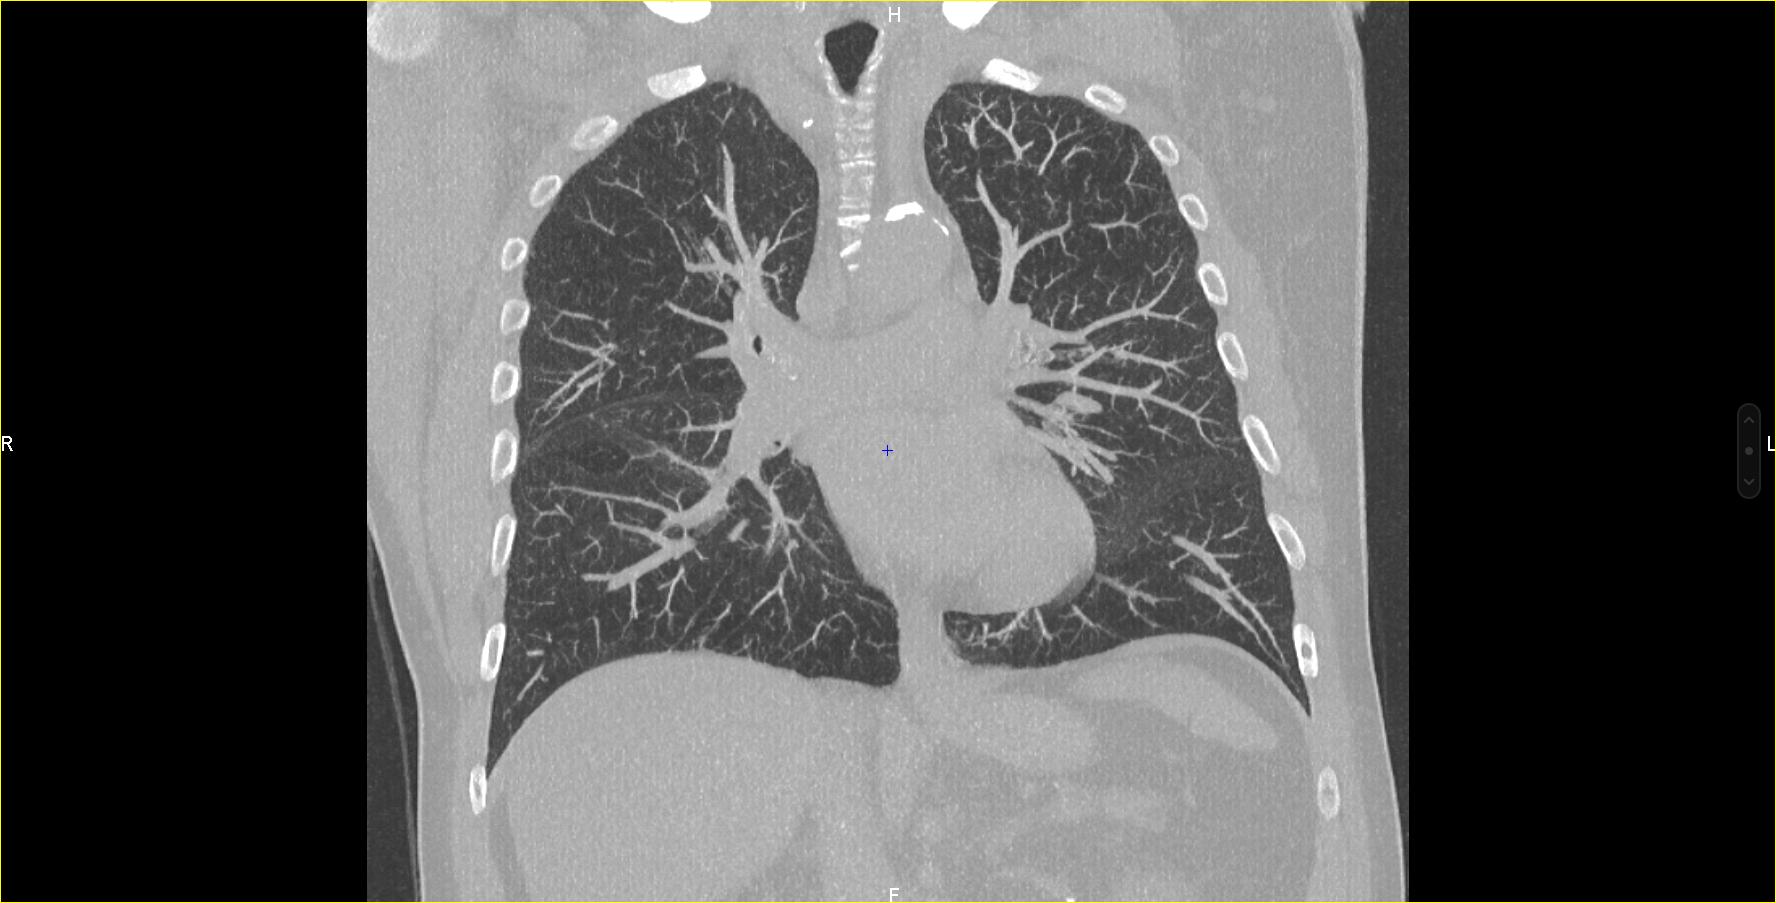

Les examens scanner : le scanner thoracique, l’angioscanner, le coroscanner...

- Scanner thoracique : L’examen de référence pour le diagnostic et le suivi des pathologies pulmonaires (pneumopathie infectieuse, cancer broncho-pulmonaire, dépistage, pneumopathie interstitielle…)

- Angioscanner artériel et/ou veineux : pour visualiser les vaisseaux sanguins. Cet examen nécessite l’injection de contraste iodé dans les vaisseaux pour diagnostiquer les sténoses vasculaires, les anévrismes de l’aorte abdominale ou de ses branches, les malformations et pour guider les interventions chirurgicales. L’angioscanner est également l’examen de choix pour diagnostiquer l’embolie pulmonaire.